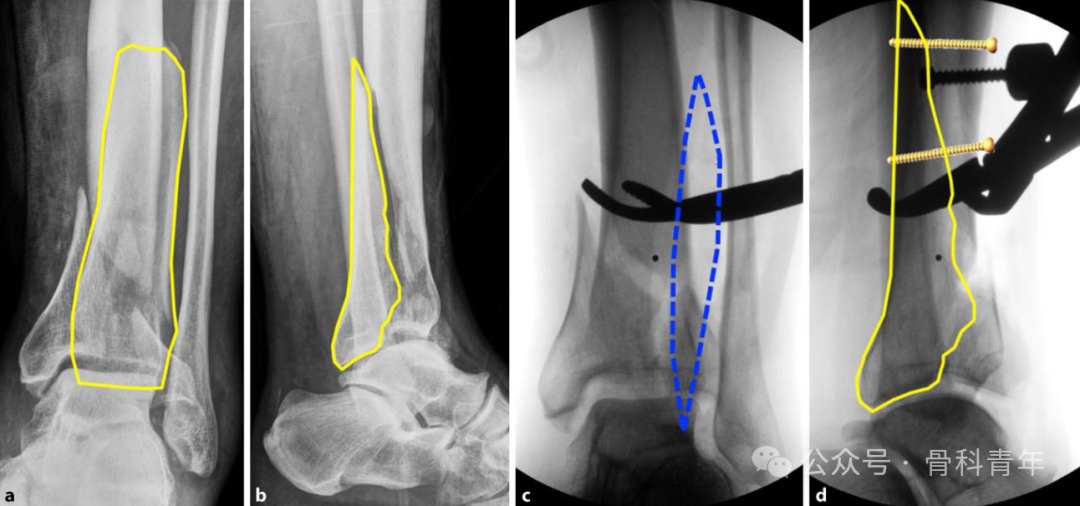

腓骨完整时,胫骨承受轴向压力而发生的骨折(a); -

胫骨内翻畸形,外侧受牵拉力,内侧受压力(b); -

胫骨外翻畸形,外侧受压力(c);